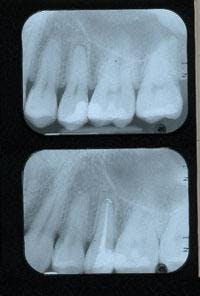

As a result of these discoveries, my fear of the pulp and dread of performing root canals are now distant memories (Figure 2). I now practice endodontics in fewer steps while achieving great results for my patients (Figure 3). Root canal treatment can and should be a part of every general practice. Endodontics is a procedure that is not only enjoyable, but satisfying and profitable as well. The phenomenal growth in endodontic technology and the myriad of resources available to improve our knowledge and simplify root canal procedures have paved new roads for the general practitioner. And with each new product that is introduced, endodontics will continue to become more simplified. If you have been avoiding endodontics in your office, maybe it’s time to start your own journey toward discovering endodontic ease. ■